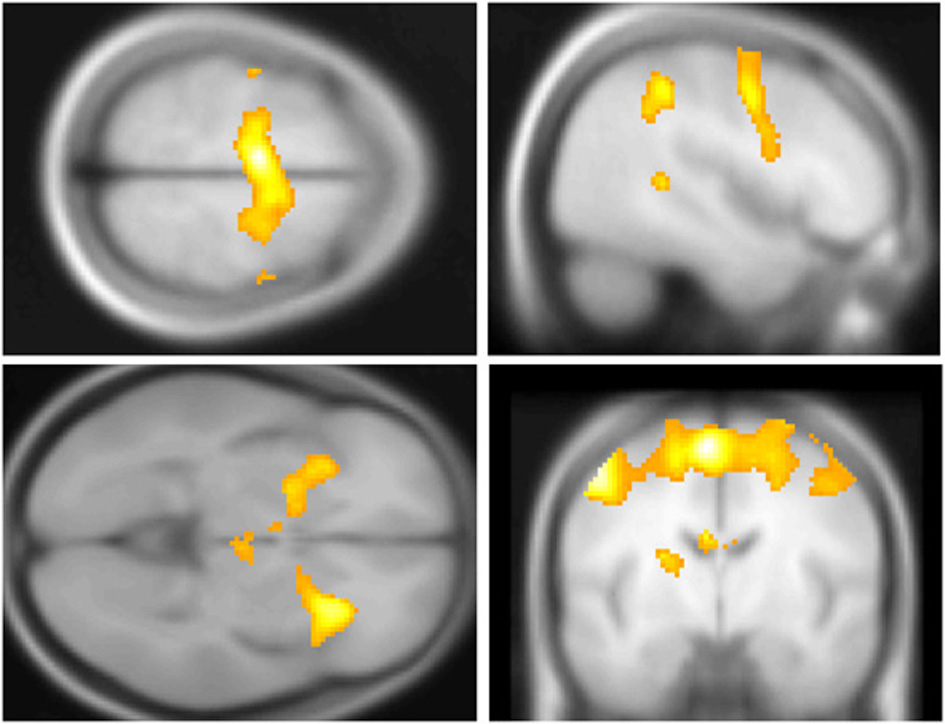

Across participants, correct stops elicited significant BOLD activations throughout the canonical motor inhibition network, including bilateral anterior insula, superior parietal lobes, supplementary motor areas, and bilateral putamen (Hester et al., 2005; Wager et al., 2005; Verbruggen and Logan, 2008). Robust deactivations were observed in the DMN (dorsal mPFC and precuneus) as well as primary and secondary visual cortices (see Tables 3, 4, Figures 3, 4, for a complete summary of Stop-related responses). The Aware > Unaware contrast revealed significant activations in the salience and frontal-parietal attention networks (Seeley et al., 2007), including right anterior insula, thalamus, caudate nucleus, mid-cingulate cortex, middle frontal gyrus, and bilateral dorsolateral/rostral prefrontal cortex. Interestingly, we also observed significant activation of bilateral inferior parietal cortex, a region of the DMN, during aware errors. See Table 5 and Figure 5 for a complete summary of Aware > Unaware responses.

FIGURE 5

www.frontiersin.org

Figure 5. Salience and default mode network BOLD responses to Aware > Unaware Errors. During conscious error monitoring we observed significant activations throughout the salience and control networks, including mid-cingulate (top right), middle frontal, dorsolateral prefrontal, bilateral caudate (bottom right), right insula (bottom right), superior, and inferior parietal cortex (bottom left) activations. Note that in addition to common salience and error related regions, we observed bilateral inferior parietal responses to this contrast, i.e., co-activation of salience and DMN. Statistical parametric map (pFWE < 0.05, k threshold > 5 contiguous voxels) superimposed on SPM canonical anatomical image, average of 305 T1-weighted images. Top left “glass brain” displays activation extent in three dimensional space. Top right shown at MNI X coordinate = 1, bottom left at X = −43. Bottom right shown at Z = 1. See Table 5 for a complete list of foci.